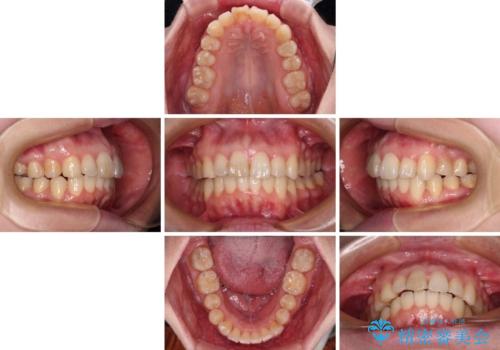

- 上顎前歯の突出感と、前歯のクロスバイトを気にして来院された患者様です。

前歯の叢生と口元の閉じにくさを気にして来院された患者様です。

奥歯の咬み合わせを見ると、上顎が下顎に対して相対的に前方にありました。

カリエール・ディスタライザーを用いたことで上顎前歯の突出感はスムーズに解消され、歯列不正は1年半ほどでほぼ改善することができました。

しかし、その後インビザライン特有の奥歯がうまく噛めないという問題が長引き、改善に1年近い期間を要することとなりました。